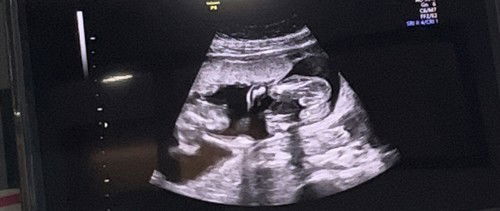

Hasil usg jk

Bun dokter saya masih ragu, katanya kemungkinan cowo, saya jadi penasaran, menurut bunda2 ini cewe atau cowo yaa?